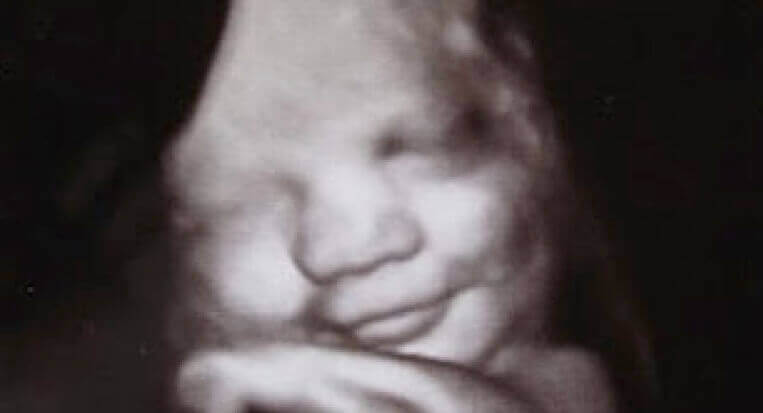

감정만큼 신비로운 면모를 가진 것은 매우 흔하지 않다. 인간이 문화, 교육, 성별 그리고 태어난 곳의 일부라는 사실은 부정할 수 없다. 하지만, 이것들은 우리 개개인이 가지고 있는 유전적 바탕과 이미 하나로 통합되었다. 더럼 대학과 랭커스터 대학(영국 소재)은 이것을 입증하기 위한 매력적인 연구를 하나 진행했다. 이 연구를 통해, 엄마의 자궁 속에 있는 태아가 다양하지는 않지만, 감정을 표현하는 것이 관찰되었다.

초음파를 사용해, 태아가 미소 짓고, 심지어 우는 것과 유사한 감정을 보이는 것을 관찰할 수 있었다. 이것은 차분하고 고요한 자궁이라는 세상 안에서도 인간은 이미 “활성화”를 시작한다는 것을 입증해 주었다. 태아는 인간을 생존할 수 있게 하는 가장 본능적이고, 중요한 언어를 훈련하기 시작하는 것이다. 미소는 웰빙과 만족감을 표현하는 데 도움이 된다. 울음은 효과적인 “경보 체계”로서의 기능을 수행한다. 이것을 통해, 아기는 가장 기본적인 필요를 표현하는 것이다.